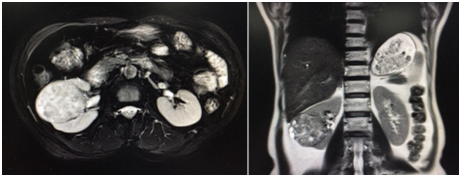

廣東的沈阿姨因為出現血尿,到醫院檢查發現右側腎臟上長了一個 5cm的大腫瘤。為了給她最好的醫療條件,家人多方打聽來到中國醫學科學院腫瘤醫院深圳醫院泌尿外科就診。

接着進來門診的是一名同行,來自深圳某醫院的小夏同樣因為檢查發現左腎一枚 6cm 的腫瘤,熟悉醫療領域的他,是慕名來到王東文教授的診室,評估病情後夏醫生也住進了泌尿外科病房。看着窗外鬱鬱蔥蔥的山景,夏醫生感慨:「深圳這麼多醫院,你們的專家和環境真是雙一流!」

沈阿姨、夏醫生入院後都完善了術前檢查。綜合腎臟腫瘤的位置、大小、深度及血管情況後,王東文教授給他們制定了 3D 腹腔鏡根治性腎切除手術方案。